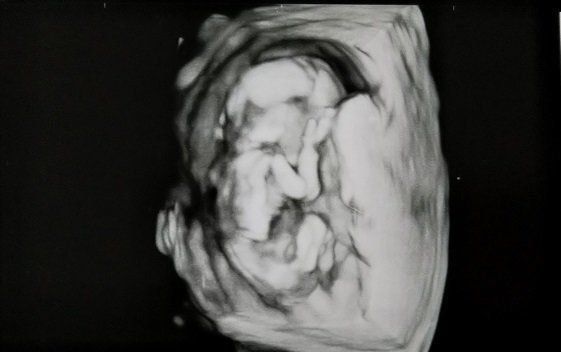

セイコさんの妊娠15週目のエコー写真 日々形をかえていく様に感動

何か窮屈そうですね。足の骨も見えて来て、すっかり人型です。幸いつわりは軽かったのですが、とにかく疲労感と眠気との闘いでした。以前は適度な運動のためにと自転車で通っていた職場ですが、妊娠してからは40分くらいかけてゆっくり歩きながら通っていました。

まきさんの妊娠15週目のエコー写真 主人もクリニックでエコーを見ました。

妊娠15週目は、主人とクリニックへ。私だけでなく、主人もエコー写真をとても楽しみにしていました。骨が見えてきたり、肉付きの様子が見えたりと、赤ちゃんの成長にともなって、エコーはだんだんリアルな画像になってきました。そして、わが子をかわいく思う気持ちは、どんどん大きくなっていきました。

こぢんまり子さんの妊娠15週目のエコー写真 つわりの吐き気がつらい状態

右側の丸いのが頭、左下が体で、こっちを向いている状態です。体の横になんとなく手が見えます。しっかりと顔の輪郭が写っています。つわりが続いて、誰もいない寝室のムワッとした残り香だけで、吐いてしまうことも。なるべく体を休ませながら、幼稚園の送り迎えと家事をこなしました。上の子たちに「おなかに赤ちゃんがいるよ」と伝えると、上の幼稚園の子は喜んでいましたが、下の子はまだよく分かっていないような感じでした。